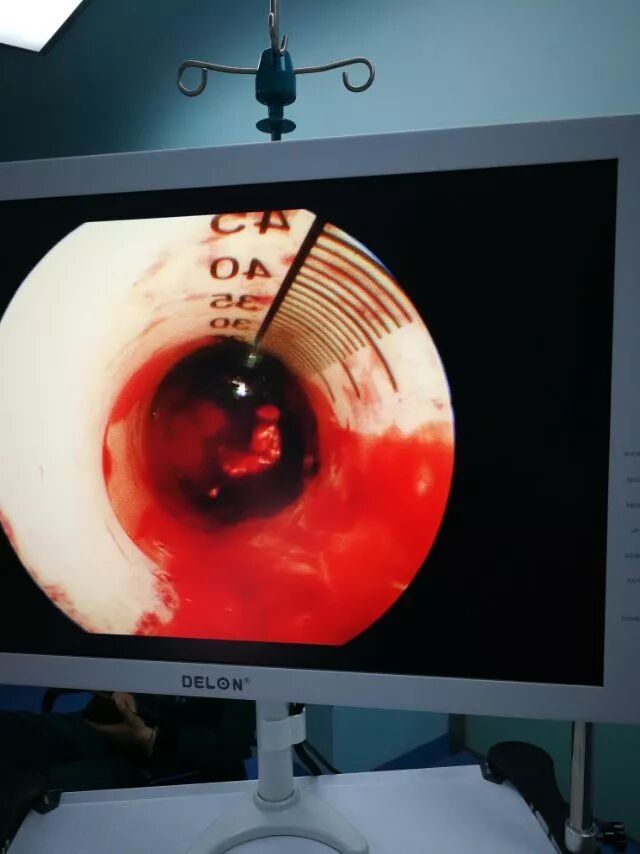

内镜下清血